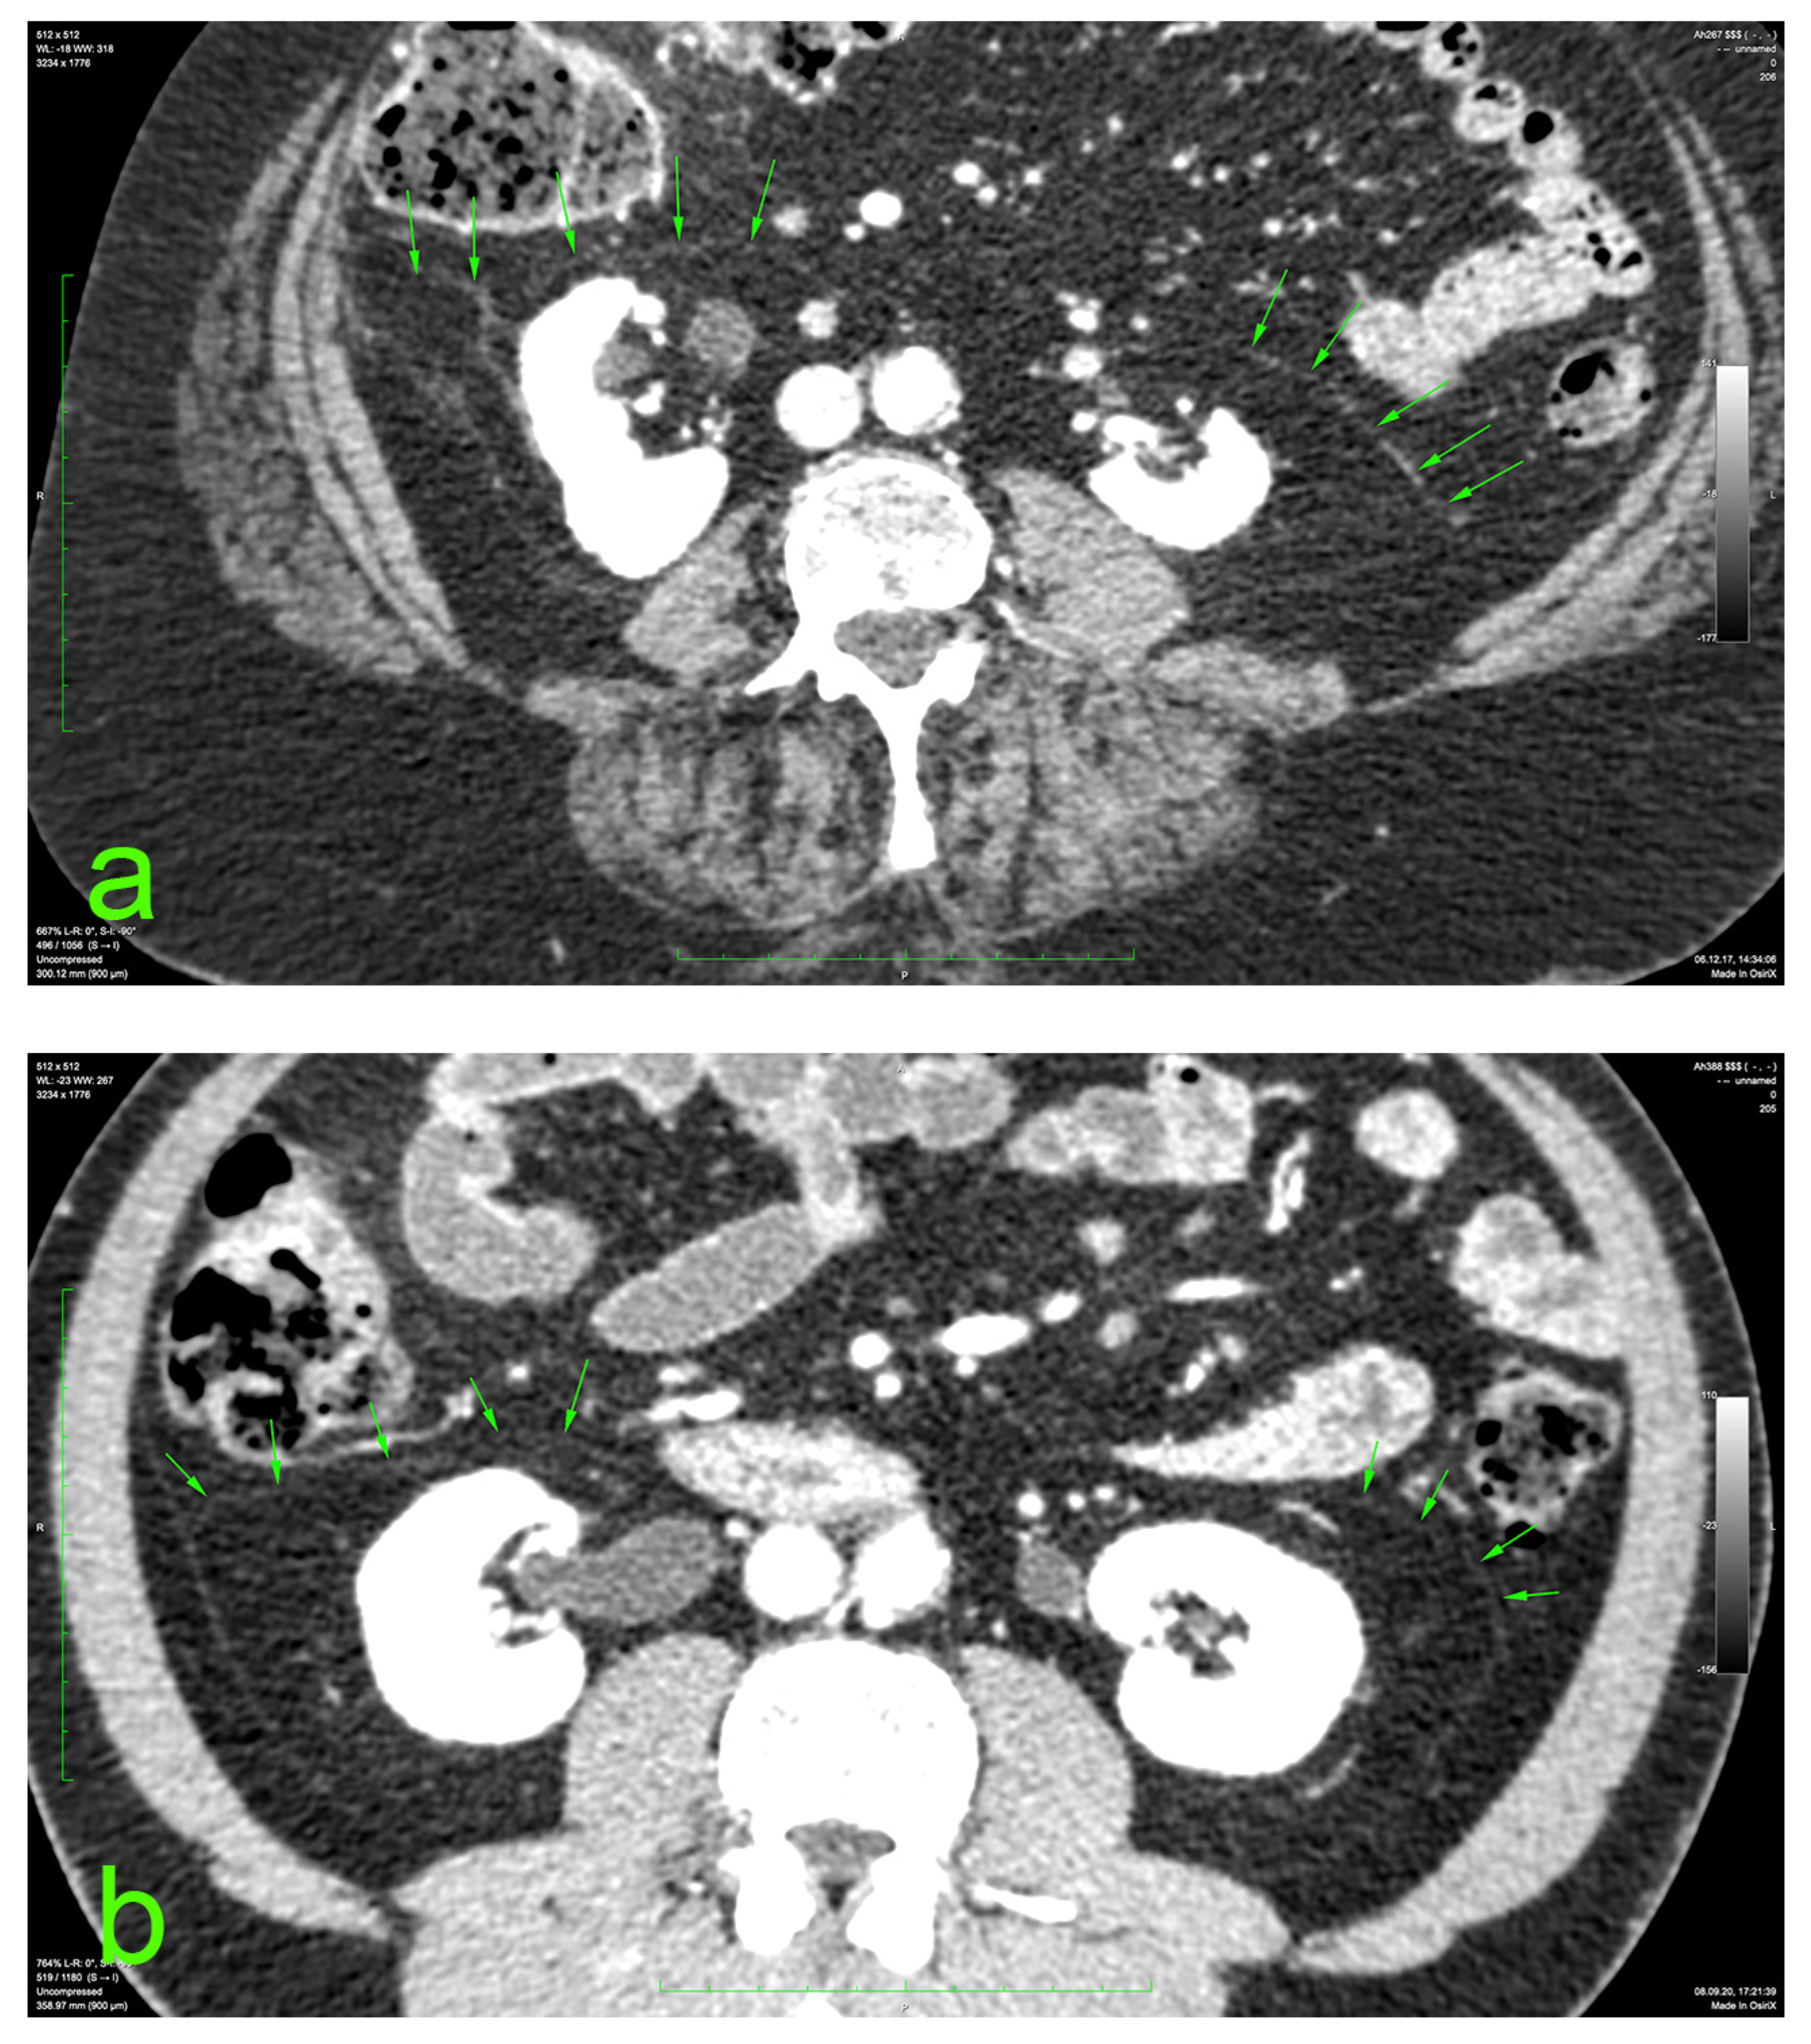

The principal portion of this study was also based on the aforementioned CT datasets. They were analyzed using a 2D multiplanar reconstruction with a maximum intensity projection with the aid of Food and Drug Administration (FDA)—approved Osirix MD v.14.0 64-bit image-processing application software (Pixmeo, Bernex, Switzerland). The wide area behind the ascending and descending colon was analyzed for the appearance of the distinct retrocolic fascia. The thickness of this fascia was measured at four arbitrary levels, related to the kidneys, on both sides (left and right): upper pole, midlevel, lower pole, and below the lower kidney pole. Each measurement was performed twice, calculating the arithmetic mean for each level. The final thickness (tool Length) of one side was defined as the mean value of the four measurements (Figure 1).

Figure 1. Prerenal fasciae (green arrows) on injected CT: (a) 70-year-old female patient with a BMI of 32.9; (b) 50-year-old male patient with a BMI of 30.1.